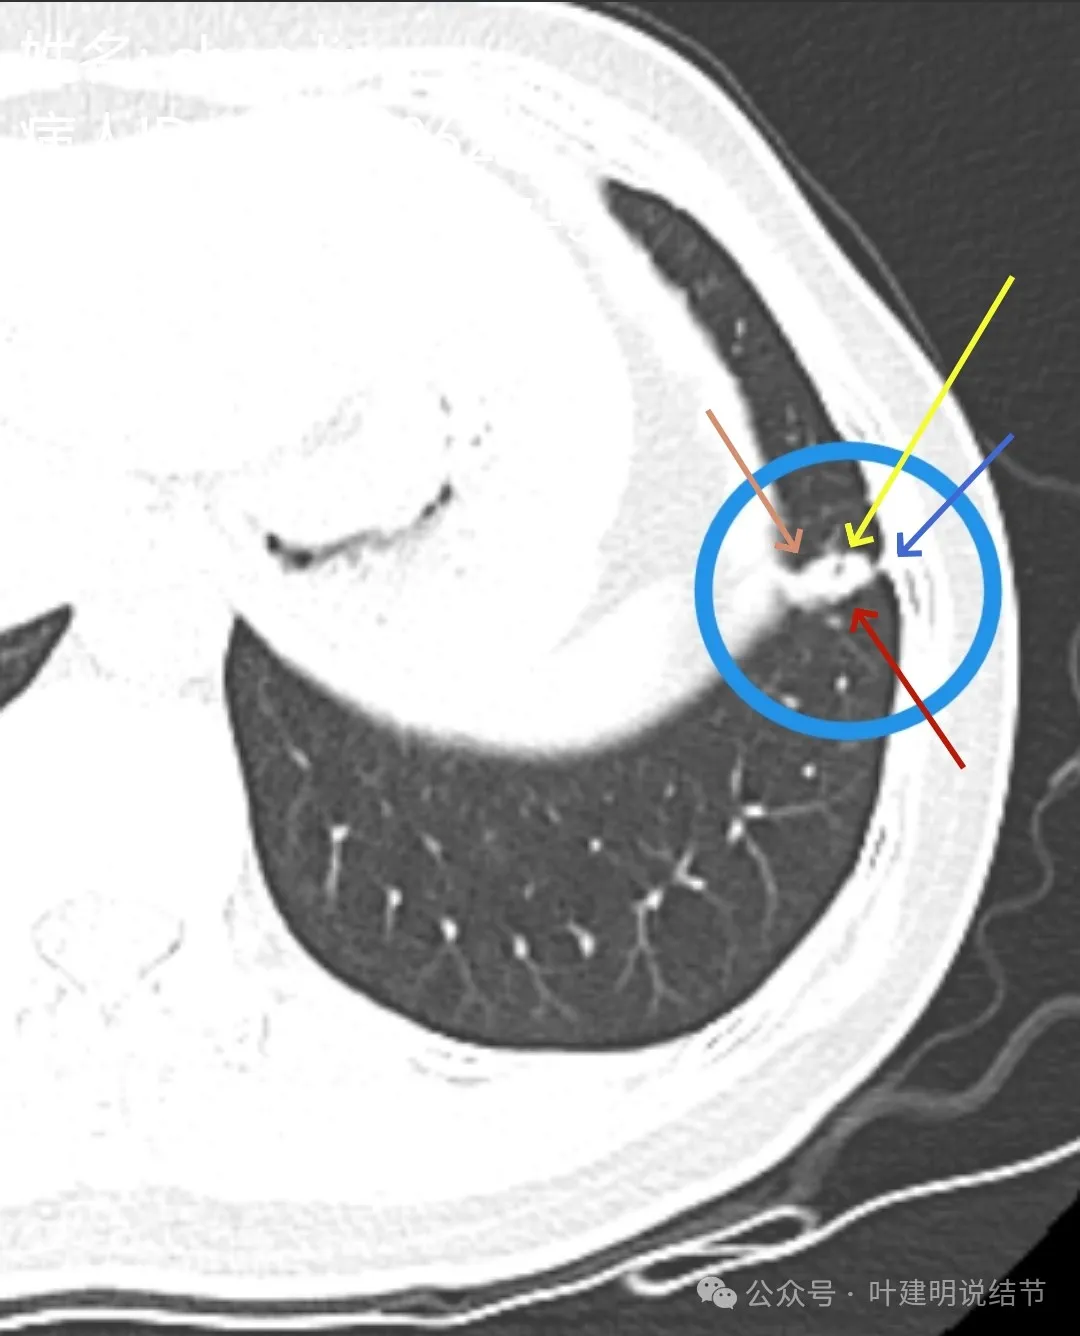

影像展示与分析:

左下叶主病灶实性,收缩力较弱,胸膜略有牵拉,表面似乎较为光滑,毛刺不明显,血管征不明显,整体密度显得较高。

局部放大了看,边缘略毛糙;胸膜略牵拉;灶内有小区域密度偏低的空泡或偏低密度区;表面似有较为勉强的分叶征的样子。但整体说不上明显收缩力,磨玻璃成分也不大明显。

我看有所异常的就是这几处(次要病灶未展示)。桔色圈起来的过小过淡的磨玻璃结节,考虑肺泡上皮增生可能性大,感觉没到不典型增生,先年度随访;黄色圈起来的微小实性,考虑良性的;蓝色的这处密度高,似乎良性的可能性大,但一是随访有增大,二是有胸膜牵拉,三是位置好,而若真恶性,实性风险大。我个人倾向4-6个月后左下叶靶扫描下,如果有恶性可能,则还是手术切了化验比较放心。意见供参考!